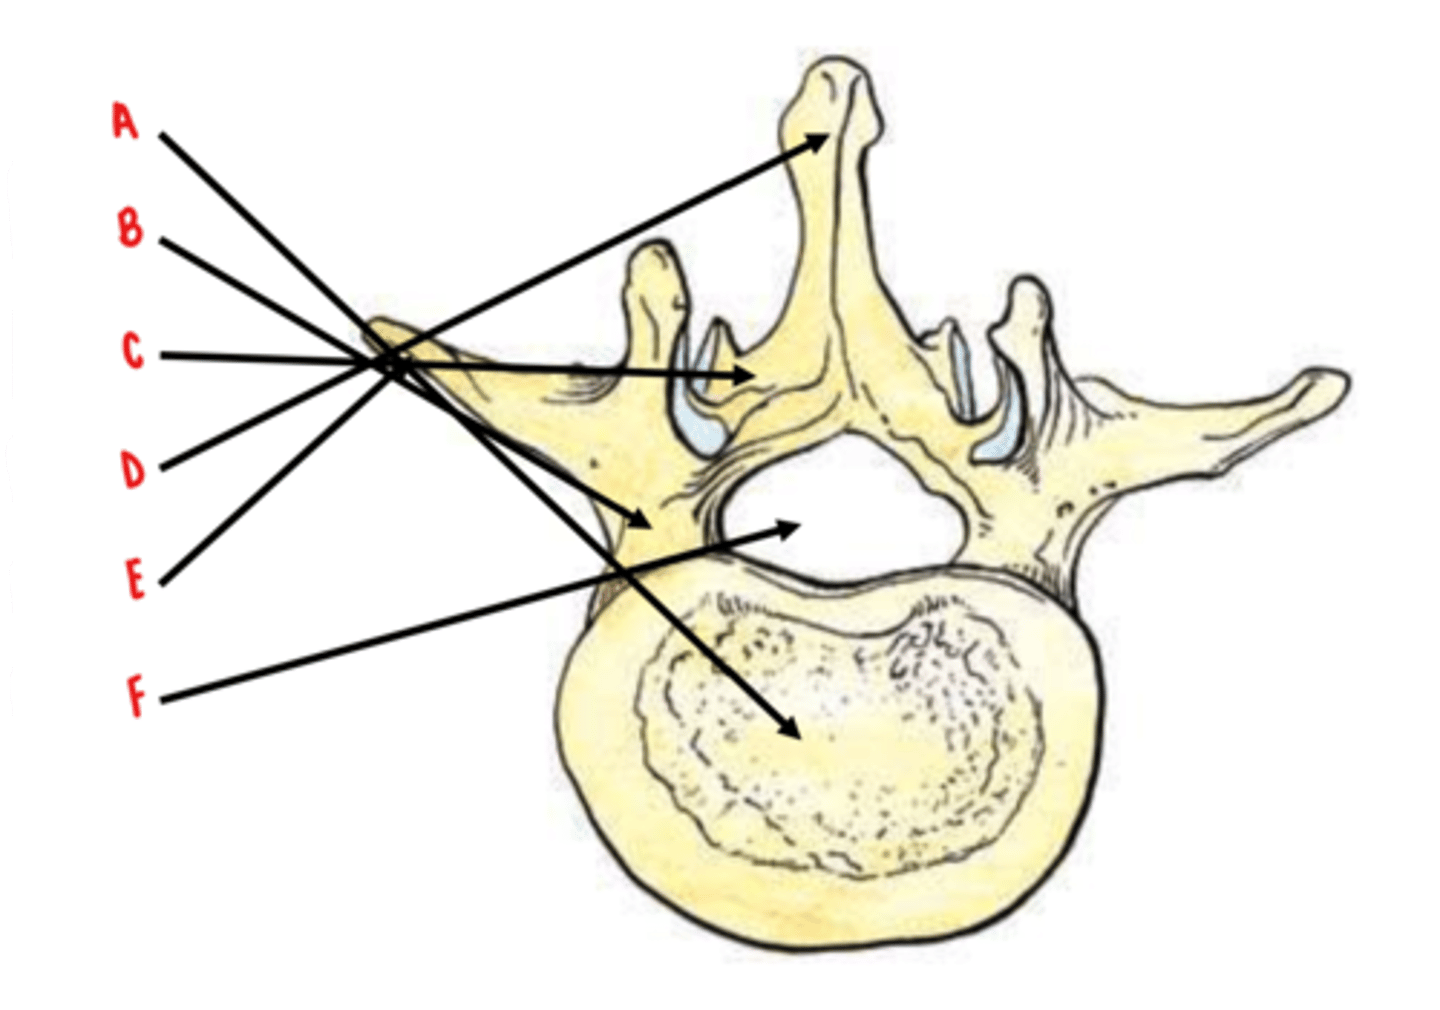

body

Identify A

pedicles

Identify B

laminae

Identify C

spinous process

Identify D

transverse process

Identify E

vertebral foramen

Identify F